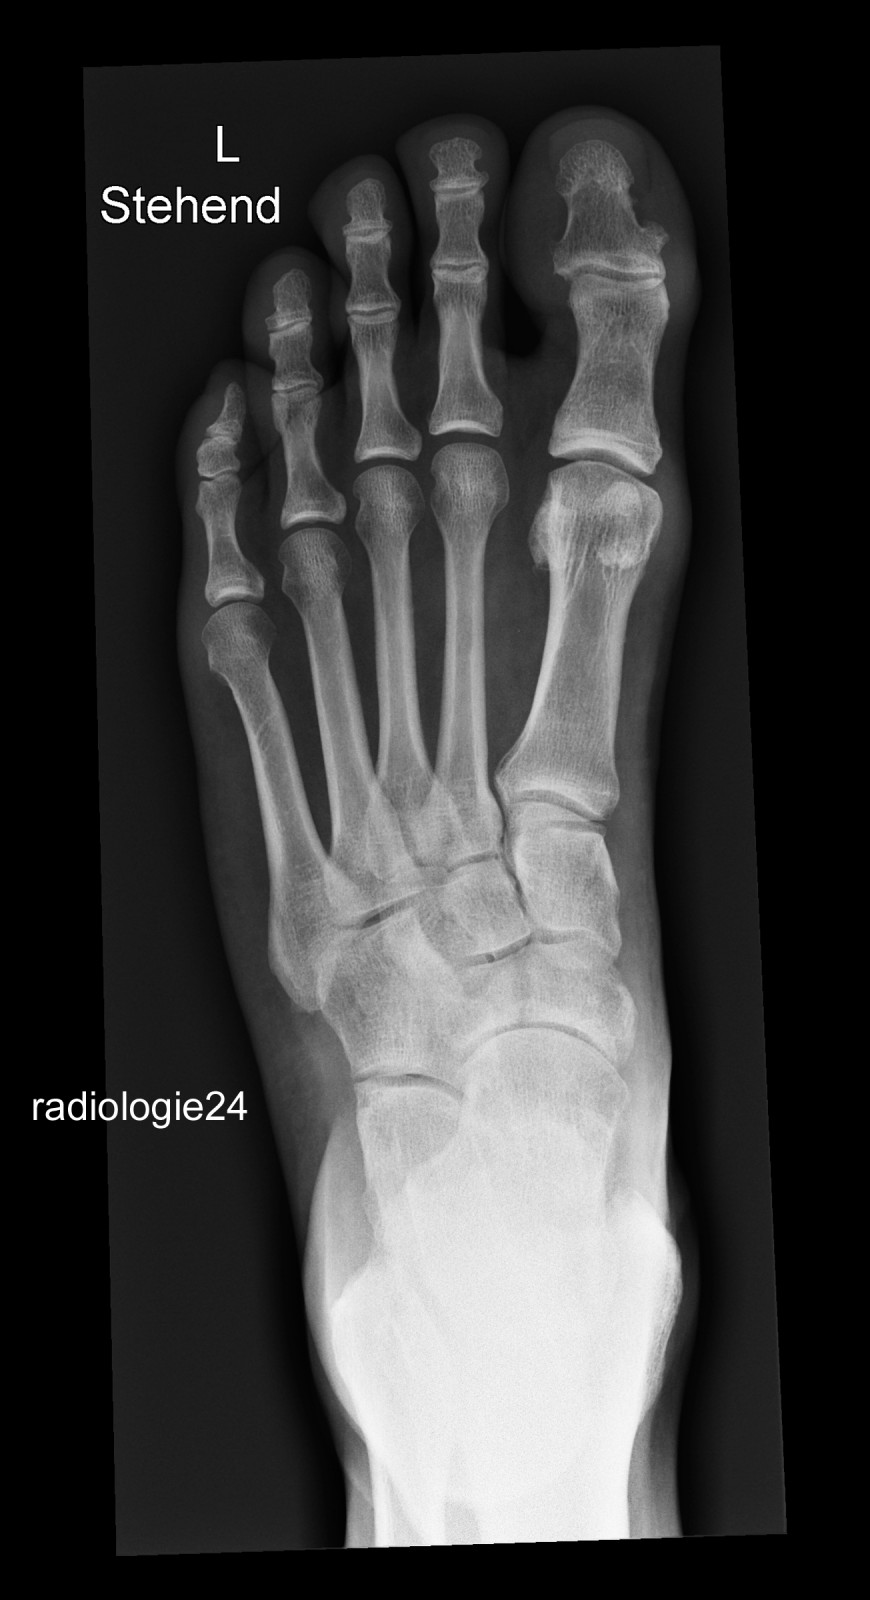

Röntgenfall des Monats September 2018 mit Auflösung

52 jähriger Patient Fehltritt beim Wandern. Schmerzen Mittelfuss. Ihre Diagnose? Weitere radiologische Diagnostik notwendig?

Bild vergrössern

Link zur Auflösung mit ausführlichem Befund:

https://www.radiologie24.ch/radiologie-mediathek/roentgenfall_des_monats